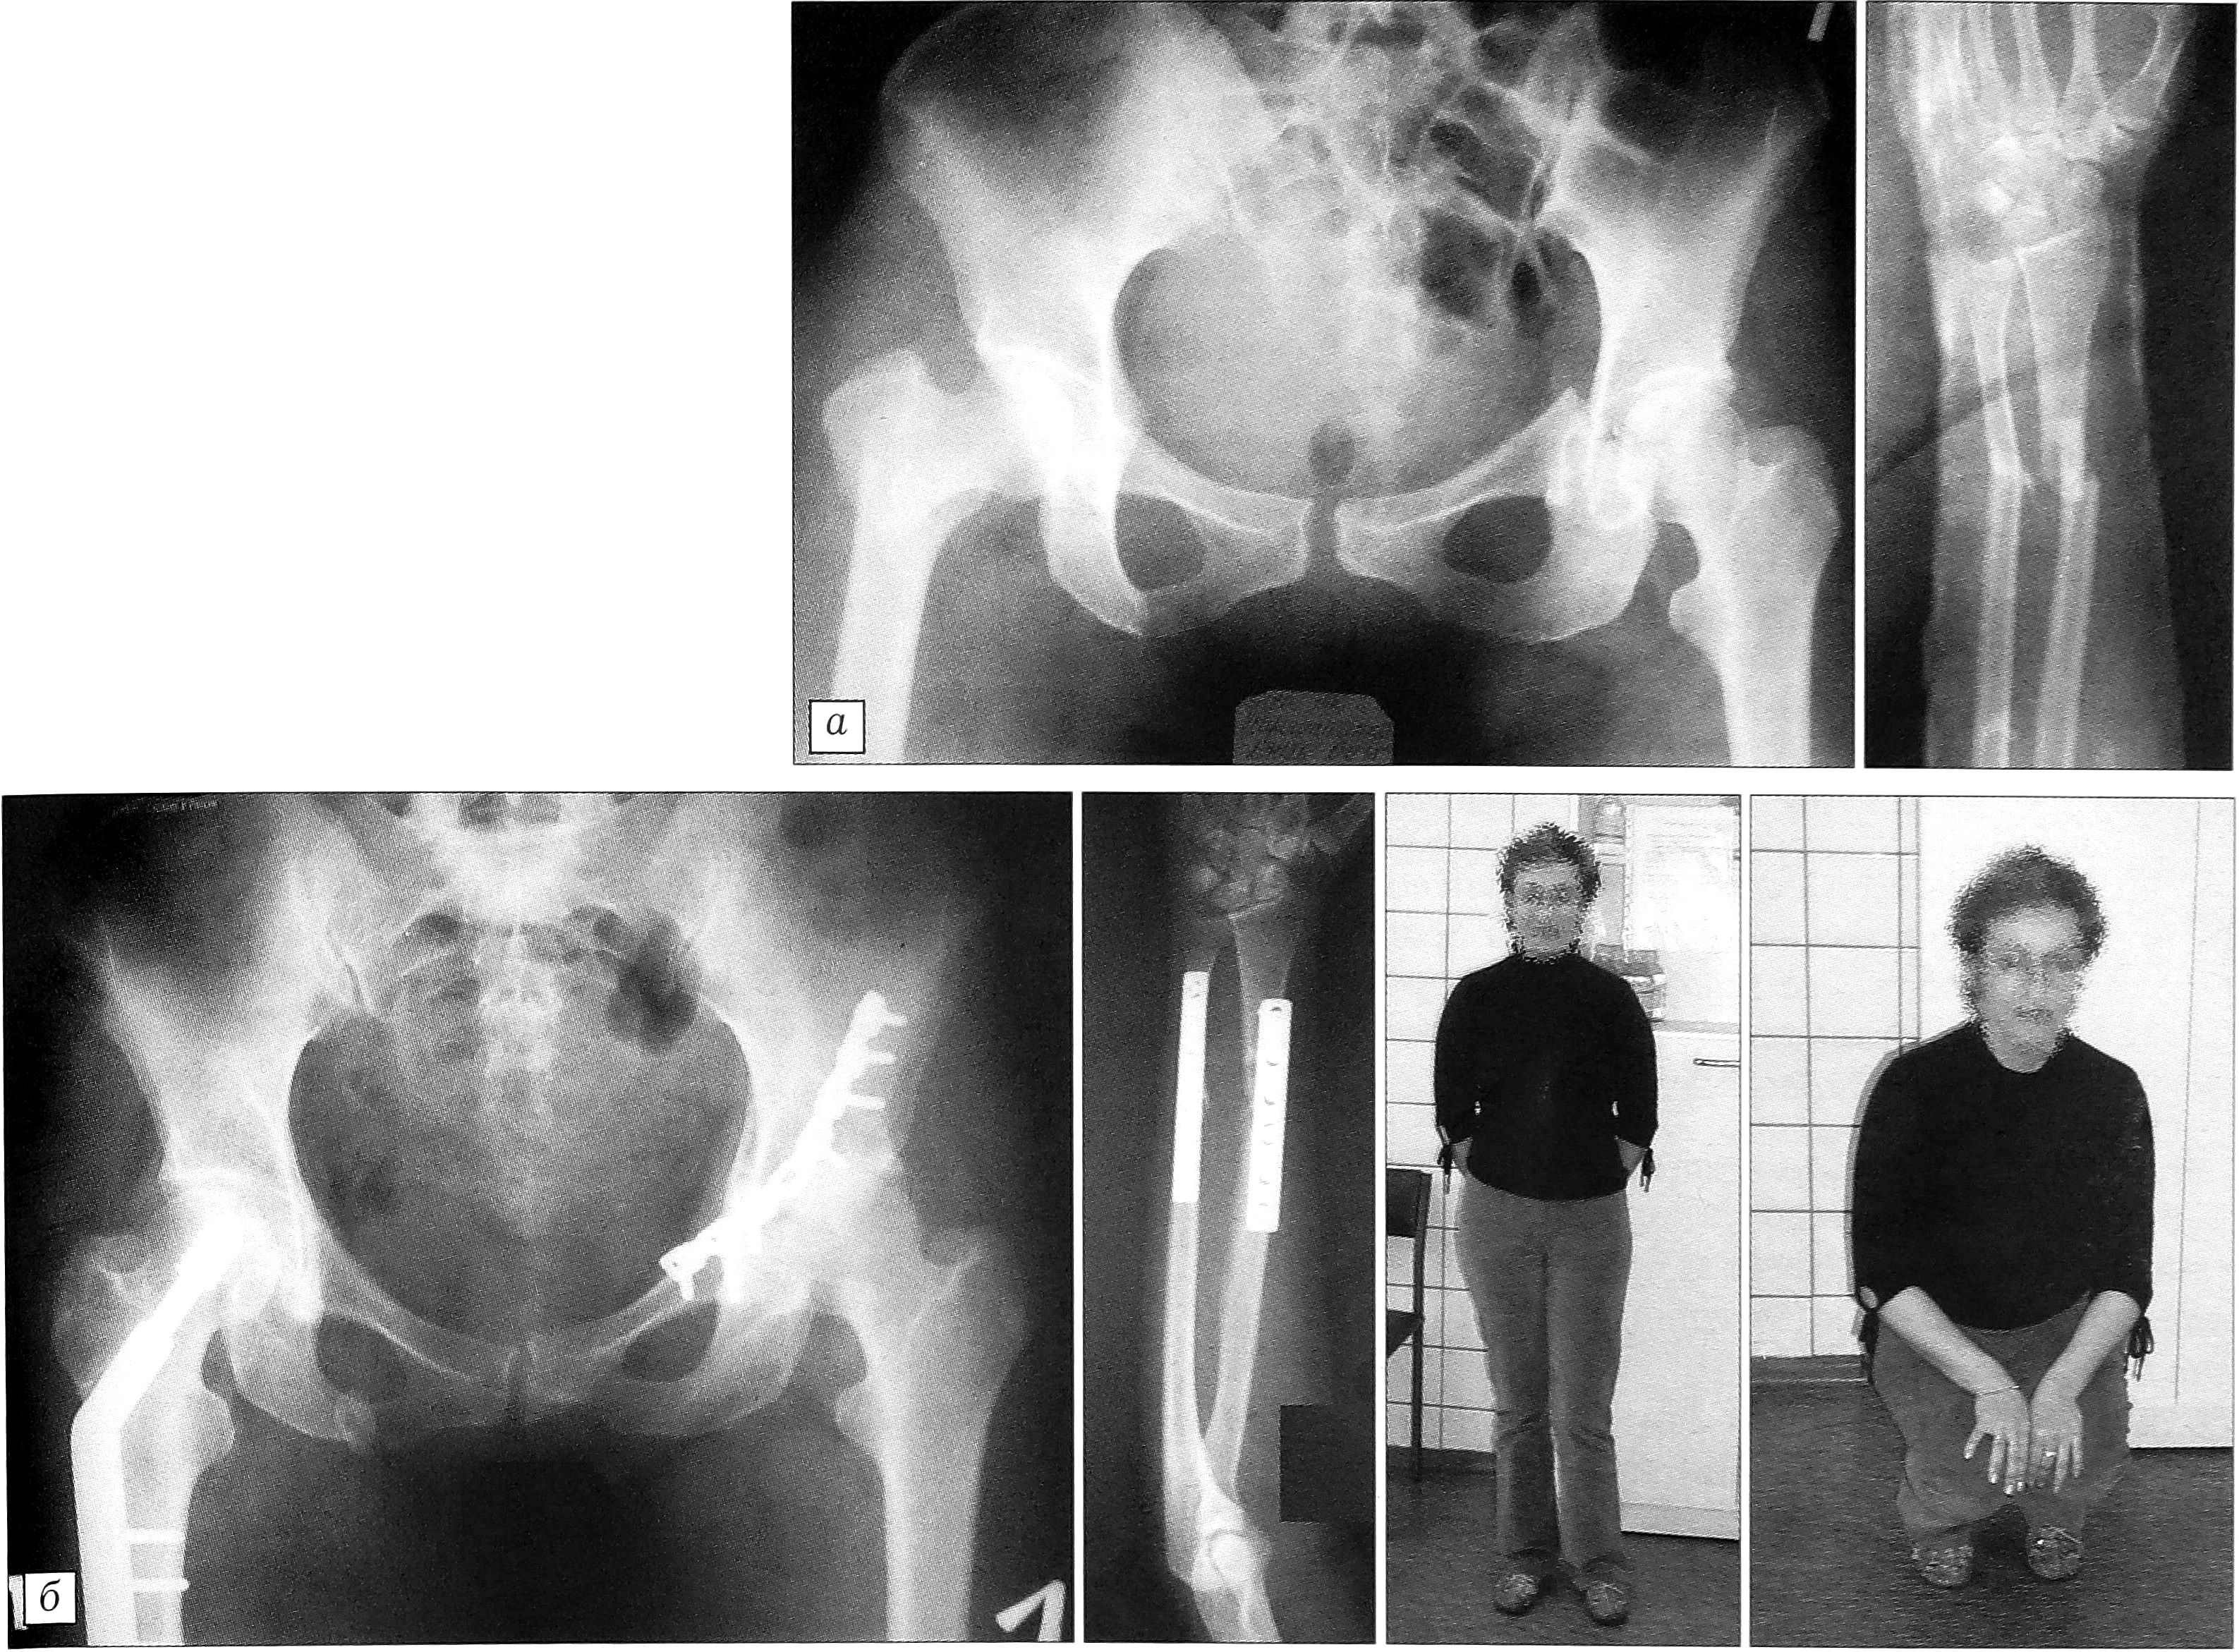

Пример. Больная М.,34 лет, переведена из загородной больницы 16.08.01 на 7-е сутки после травмы с диагнозом: тяжелая сочетанная травма — чрезвертлужный перелом таза слева, закрытый чрезвертельный перелом правого бедра, закрытый перелом обеих костей левого предплечья в средней трети со смещением отломков, переломы ребер слева, сотрясение головного мозга (рис. 3, а). Правое бедро было иммобилизовано скелетным вытяжением за проксимальный метафиз большеберцовой кости, левое предплечье — гипсовой повязкой. После проведения предоперационной подготовки, на 12-е сутки с момента травмы, одномоментно последовательно-параллельно выполнены остеосинтез вертлужной впадины реконструктивной пластиной, остеосинтез правого бедра фиксатором DHS и остеосинтез костей левого предплечья пластинами. Послеоперационный период протекал без осложнений. Нагрузка на правую ногу разрешена через 8 нед после операции, на левую — через 5 мес. Пациентка осмотрена через 1 год: все переломы срослись, наступило полное функциональное восстановление (рис. 3, б).

Рис. 3. Больная М. 34 лет. Сочетанная травма. Чрезвертлужный перелом таза слева, закрытый чрезвертельный перелом правого бедра, закрытый перелом обеих костей левого предплечья в средней трети со смещением отломков. а — рентгенограммы при поступлении; б — рентгенограммы и функциональный результат через 1 год.